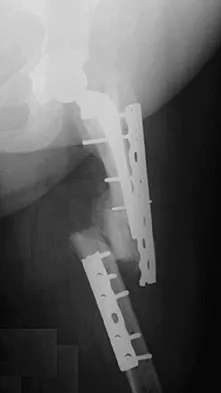

Figures 7a and 7b show the radiographs of a 51-year-old woman who injured her left leg after falling off a stepladder. Surgical reconstruction is performed with a compression screw and side plate; the postoperative radiograph is shown in Figure 7c. Following gradual progression of weight bearing, she reports that she slipped again and placed full weight on the extremity. She now notes a new onset of increased pain in her left thigh and hip region. Follow-up radiographs are shown in Figures 7d and 7e. Reconstruction should consist of

Explanation

The initial fracture was an unstable reverse oblique intertrochanteric fracture with subtrochanteric extension. Initial fixation with a high-angled screw and side plate construct may not provide stability as well as a 95 degree fixed-angle device or a intramedullary hip screw device. The follow-up radiographs show loss of fixation and further propagation of the fracture distally. Reconstruction would best be accomplished with hardware removal and conversion to a long intramedullary nail with femoral head fixation or a 95 degree angled plate and screw device. Conversion to a longer plate does not improve the biomechanical situation at the primary fracture site. In situ bone grafting would not provide any additional stability and would not correct the deformity. The proximal femoral fracture is not amenable to retrograde nailing. Cerclage wiring will not sufficiently enhance stability and is not indicated. Bridle SH, Patel AD, Bircher M, Calvert PT: Fixation of intertrochanteric fractures of the femur: A randomized prospective comparison of a gamma nail and dynamic hip screw. J Bone Joint Surg Br 1991;73:330-334. DeLee JC: Fractures and dislocations of the hip, in Rockwood CA Jr, Green DP, Bucholz RW, Heckman JD (eds): Rockwood and Green's Fractures in Adults, ed 4. Philadelphia, PA, Lippincott-Raven, 1996, pp 1659-1825. Haidukewych GJ, Israel TA, Berry DJ: Reverse obliquity fractures of the intertrochanteric region of the femur. J Bone Joint Surg Am 2001;83:643-650.